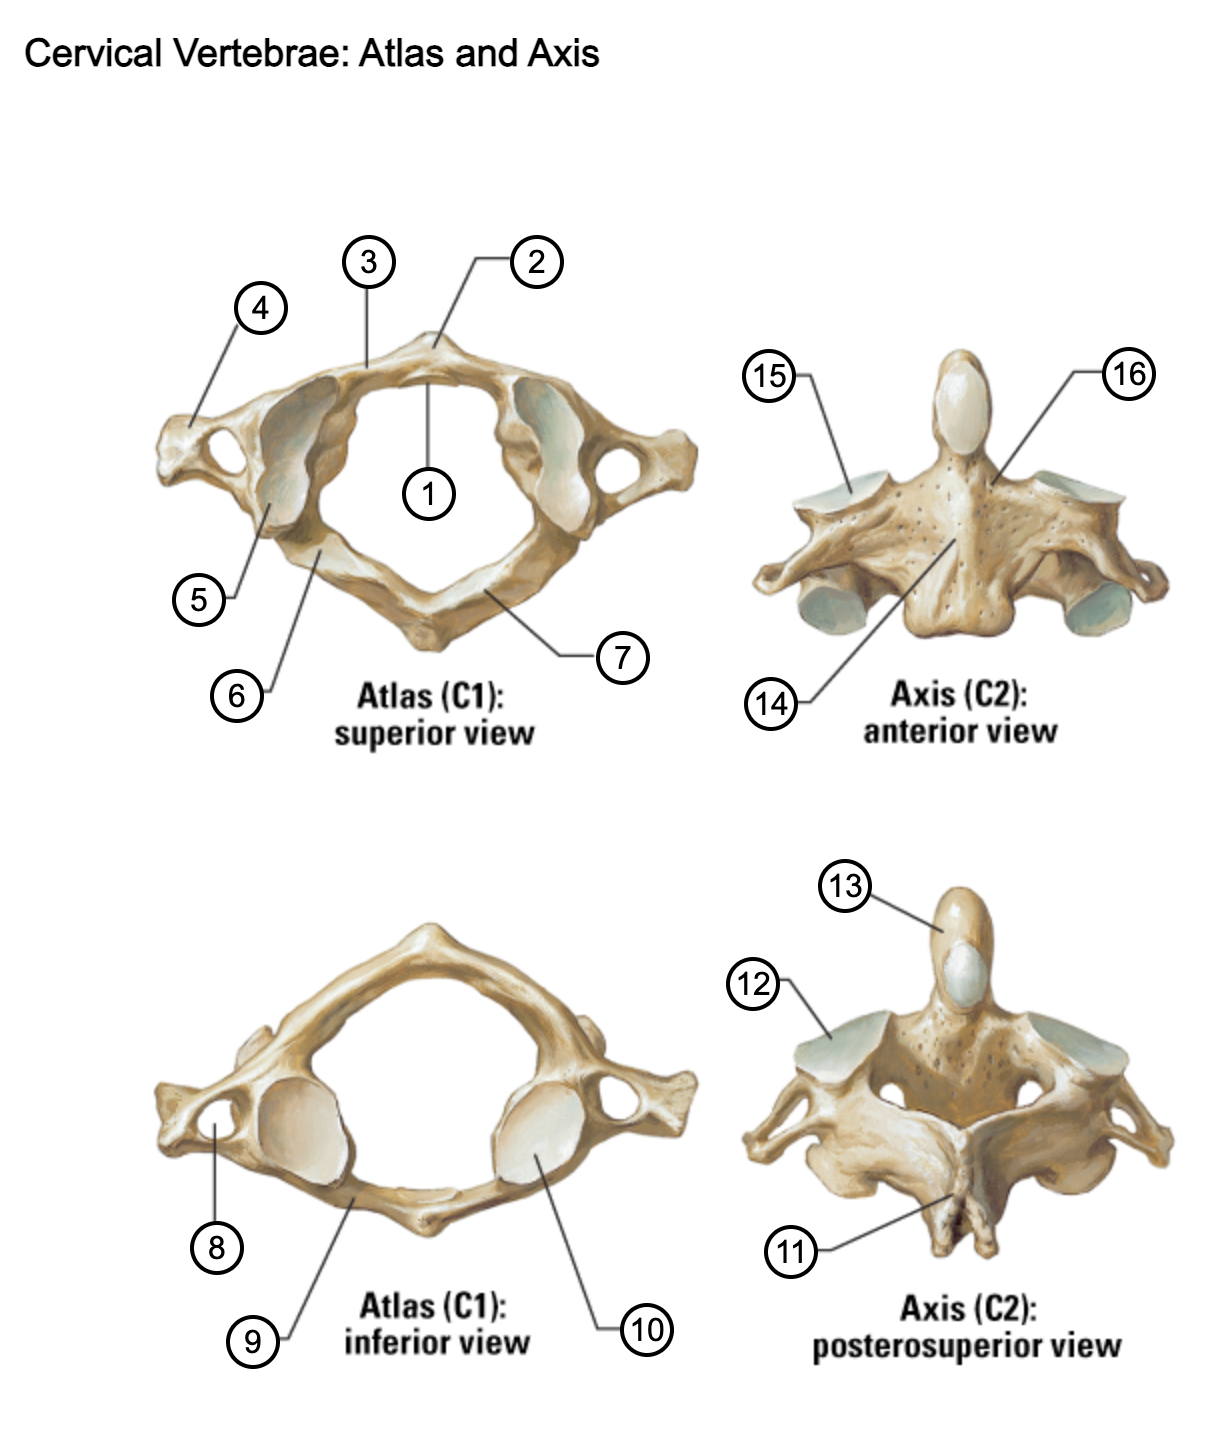

1

facet for dens

2

anterior tubercle

3

anterior arch

4

transverse process

5

superior articular surface of atlas

6

groove for vertebral artery

7

posterior arch

8

transverse foramen

9

anterior arch

10

inferior articular surface of atlas

11

spinous process

12

superior articular facet

13

dens of axis

14

body of axis

15

superior articular facet for atlas

16

pedicle of vertebral arch